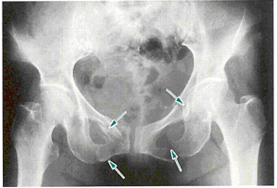

両側恥骨上下肢骨折とは、両側の恥骨と坐骨の骨折です。骨盤輪の連続性が損なわれています。straddle骨折とも言います。

両側恥骨上下肢骨折(straddle骨折)

マルゲーニュ骨折とは、前方骨盤輪骨折と後方骨盤輪骨折が合併した骨折で垂直方向にずれているものです。安定性が失われ、骨盤片は下肢とともに情報に転位するため、下肢が短縮しているようにみえます。